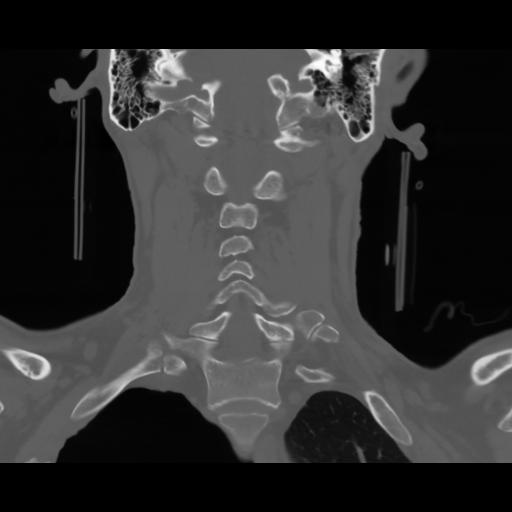

13 P.BLANDAS,,Coronal,2.000,P.BLANDAS,Coronal,